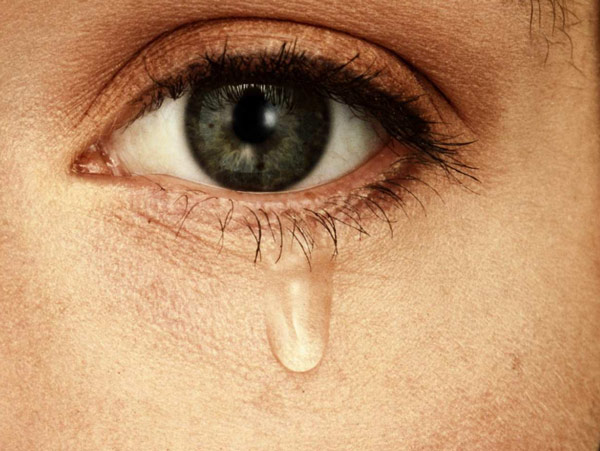

কে বলল, চোখের জলের হয় না কোনও দাম?

এ বার চোখের জলও ‘কেনা’ যাবে! চোখের জল জমিয়ে রাখা যাবে। চোখের জল দেওয়া, নেওয়ার জন্য এ বার চালু হচ্ছে টিয়ার্স ব্যাঙ্ক। সেই ব্যাঙ্কে চোখের জল দেওয়া বা সেখান থেকে চোখের জল নেওয়ার জন্য এ বার অ্যাকাউন্ট খোলা যাবে চোখের জলের ব্যাঙ্কে। রীতিমতো দাম চুকিয়েই চোখের জল নিতে হবে এ বার ওই টিয়ার্স ব্যাঙ্ক থেকে। বিভিন্ন প্রয়োজনে। বিজ্ঞানীদের গবেষণায়। বিভিন্ন ওষুধ প্রস্তুতকারী সংস্থার রিসার্চ সেলের চাহিদা মেটাতে। ব্লাড ব্যাঙ্ক ও প্রতিস্থাপন, গবেষণার জন্য কিডনি, ফুসফুস সহ বিভিন্ন অঙ্গ-প্রত্যঙ্গের ব্যাঙ্কের পর এ বার চালু হতে চলেছে টিয়ার্স ব্যাঙ্কও।

কেন চোখের জলে ভিজিয়ে দিলেম না...

সম্প্রতি কলকাতায় তাঁর এক পারিবারিক বন্ধুর কাছে ঘুরতে এসেছিলেন সবেল। আনন্দবাজারকে বললেন, ‘‘আমরা দীর্ঘ দিন ধরে গবেষণা করছি চোখের জল নিয়ে। একেবারে হালে আমরা গবেষণায় দেখেছি, মানুষের চোখের জল সব সময়েই রাসায়নিক বার্তা বা সংকেত (কেমিক্যাল সিগন্যাল) বয়ে নিয়ে বেড়ায়। কোনও মহিলার চোখে জলে থাকা ‘ফেরোমোন’ সামনে দাঁড়ানো কোনও পুরুষের শরীরে টেস্টোস্টেরন হরমোনের ক্ষরণের পরিমাণ কমিয়ে দেয়। সেই পুরুষের যৌন উত্তেজনাকে প্রশমিত করে বা তাকে যতটা সম্ভব কমানোর চেষ্টা করে বা কমিয়ে দেয়। সেই গবেষণাপত্রটি ছাপা হয়েছে বিজ্ঞান-জার্নাল ‘সায়েন্স’-এ।

আমরা দুঃখ পেলে কাঁদি, খুব আনন্দ হলেও কাঁদি, খুব জোরে হাসতে হাসতেও আমাদের চোখ থেকে জল গড়িয়ে পড়ে। পেঁয়াজ কাটতে গিয়ে তার ঝাঁঝ লাগলে আমাদের চোখ থেকে জল বেরিয়ে আসে। আবহাওয়ায় গরম ও ঠাণ্ডার ফারাকটা খুব তাড়াতাড়ি ওঠা-নামা করলেও চোখ থেকে জল গড়িয়ে পড়ে। জলের অভাব নেই আমাদের চোখে। ওই অশ্রু বা টিয়ার’ই আমাদের চোখকে ভাল, সুস্থ ও তরতাজা রাখে। কর্নিয়াকে দেয় ‘শ্বাসের বাতাস’। কিন্তু মুশকিলটা হল, গবেষণার জন্য চোখের জল চট করে পাওয়া যায় না। কেউই তাঁর চোখের জল দিতে চান না। দুঃখে কাঁদা বা আনন্দে চোখের জল ফেলার সময় কেই-বা ভাবেন বলুন, একটা চামচে বা কাপে বা ছোট শিশিতে ভরে রাখি অশ্রু, পরে তা গবেষকদের হাতে তুলে দিতে হবে বলে? আর চোখের জল জমিয়ে রেখে অনেক পরে তা গবেষকদের হাতে তুলে দিলেও তো তেমন লাভ হয় না। ব্যাকটেরিয়া ও অন্যান্য পরিবেশগত কারণে তা নষ্ট হয়ে যায়। সেই চোখের জল নিয়ে আর গবেষণা করা যায় না। তাই টিয়ার্স ব্যাঙ্ক গড়ে তোলার উদ্যোগ নিয়েছি আমরা। আপাতত ইজরায়েলের রাজধানী তেল আভিভ শহরেই ওই টিয়ার্স ব্যাঙ্ক চালু হবে। পরে গবেষক ও বিভিন্ন ওষুধ প্রস্তুতকারী সংস্থার প্রয়োজনে বিভিন্ন দেশে খোলা হবে তার শাখা।’’

সহযোগী ভারতীয় গবেষক অনিতা সারেঙ্গির কথায়, ‘‘চোখের জল আমাদের ‘মুড’ কী ভাবে কতটা বদলে দেয়, মস্তিষ্কের স্নায়ুর কোন কোন কার্যকলাপ তাদের নিয়ন্ত্রণ করে, ক্ষরণের আগে নিউরনগুলি কী ভাবে চোখের কোষ, কলাগুলিকে ‘সিগন্যাল’ বা সংকেত পাঠায়, নারী ও পুরুষের চোখের জলের ফারাক কতটা, কতটা পার্থক্য থাকে তাদের রাসায়নিক উপাদানে, প্রচণ্ড খিদেয় কেন চোখে জল আসে, আবেগ-সঞ্জাত (ইমোশনাল) ও আবেগ-বিবর্জিত (নন-ইমোশনাল) চোখের জলের ফারাকটা কোথায় আর সেই ফারাকটা হয় কেন, এ সব বুঝতে সহজ করবে চোখের জলের ব্যাঙ্ক। কারণ, গবেষণার জন্য তখন চোখের জল পেতে অসুবিধা হবে না।’’

সবেল বলছেন, ‘‘আমরাই প্রথম দেখিয়েছি, চোখের জলের মাধ্যমে মানুষ তার সঙ্গী, পরিচিত, কম পরিচিত বা অপরিচিতের সঙ্গে রাসায়নিক ভাবে যোগাযোগ (কেমিক্যাল কমিউনিকেশন) গড়ে তোলে। এটাকেই বলে ‘কেমো-সিগন্যাল’। যাতে কোনও গন্ধ থাকে না। তবে তা লবণাক্ত। এর আগে ওই ‘কেমো-সিগন্যাল’ একমাত্র ব্লাইন্ড মোল র্যাট-এই পাওয়া গিয়েছিল। যদিও শিশু ও পুরুষের চোখের জল কোনও ‘কেমো-সিগন্যাল’ পাঠায় কি না, সে ব্যাপারে এখনও নিশ্চিত নই আমরা। তবে আমরা দেখেছি, ইমোশনাল চোখের জলে অনেক বেশি প্রোটিন থাকে। চোখ ভাল রাখার জন্য সাধারণ চোখের জলে অতটা পরিমাণে প্রোটিন থাকে না। এই প্রোটিন আমাদের বগলেও থাকে। আমরা এও দেখেছি, পুরুষের ঘামের গন্ধ নারীদের সেই পুরুষের প্রতি যৌন আসক্তিকে বাড়িয়ে তোলে। সেই ঘামের গন্ধ বিভিন্ন পুরুষের ক্ষেত্রে বিভিন্ন রকমের হয়। এমনকী, পুরুষের বিভিন্ন ‘মুডে’ সেই ঘামের গন্ধও হয় নানা রকমের। দেখা গিয়েছে, সদ্য মা হওয়া নারীর বক্ষ আবরণী বা জামাকাপড়ের গন্ধ অন্য নারীর (যিনি মা হননি বা আসন্নপ্রসবা নন) যৌন উত্তেজনা বাড়িয়ে দেয়।’’